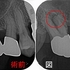

赤丸:手づかずの神経管に根尖病変

黄色丸:歯の側面にパフォレーション

先日仮歯が割れたと来院されたのでレントゲンを撮らせてもらいました。

口蓋根の根尖病変も綺麗に治ってくれています。

また、長く続いていたぐじゅぐじゅした痛みも無くなったそうです。